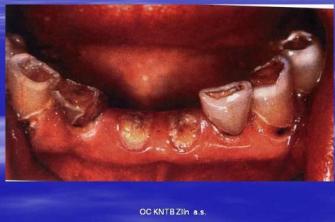

Zvýšená kazivost chrupu